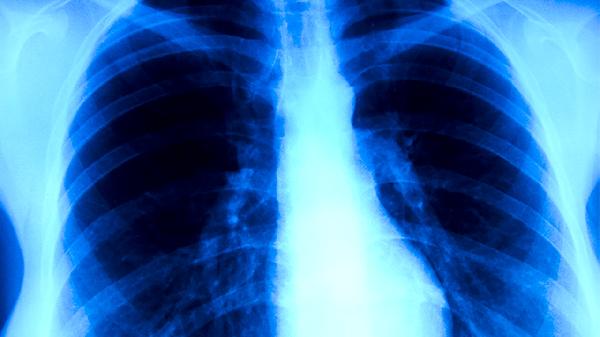

肺癌中医治疗可通过中药调理、针灸疗法、艾灸疗法、气功疗法、饮食调养等方式进行。肺癌可能与长期吸烟、环境污染、遗传因素、职业暴露、慢性肺部疾病等因素有关,通常表现为咳嗽、胸痛、咯血、呼吸困难、体重下降等症状。